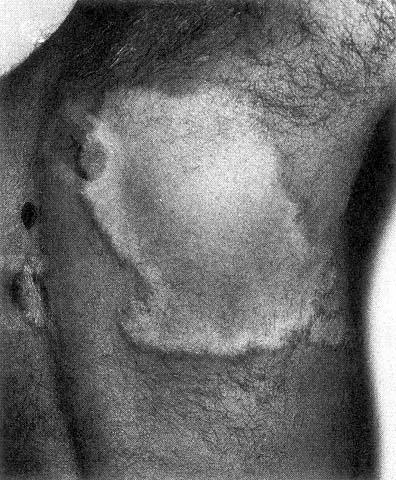

TUBERKULÖSE LEPRA